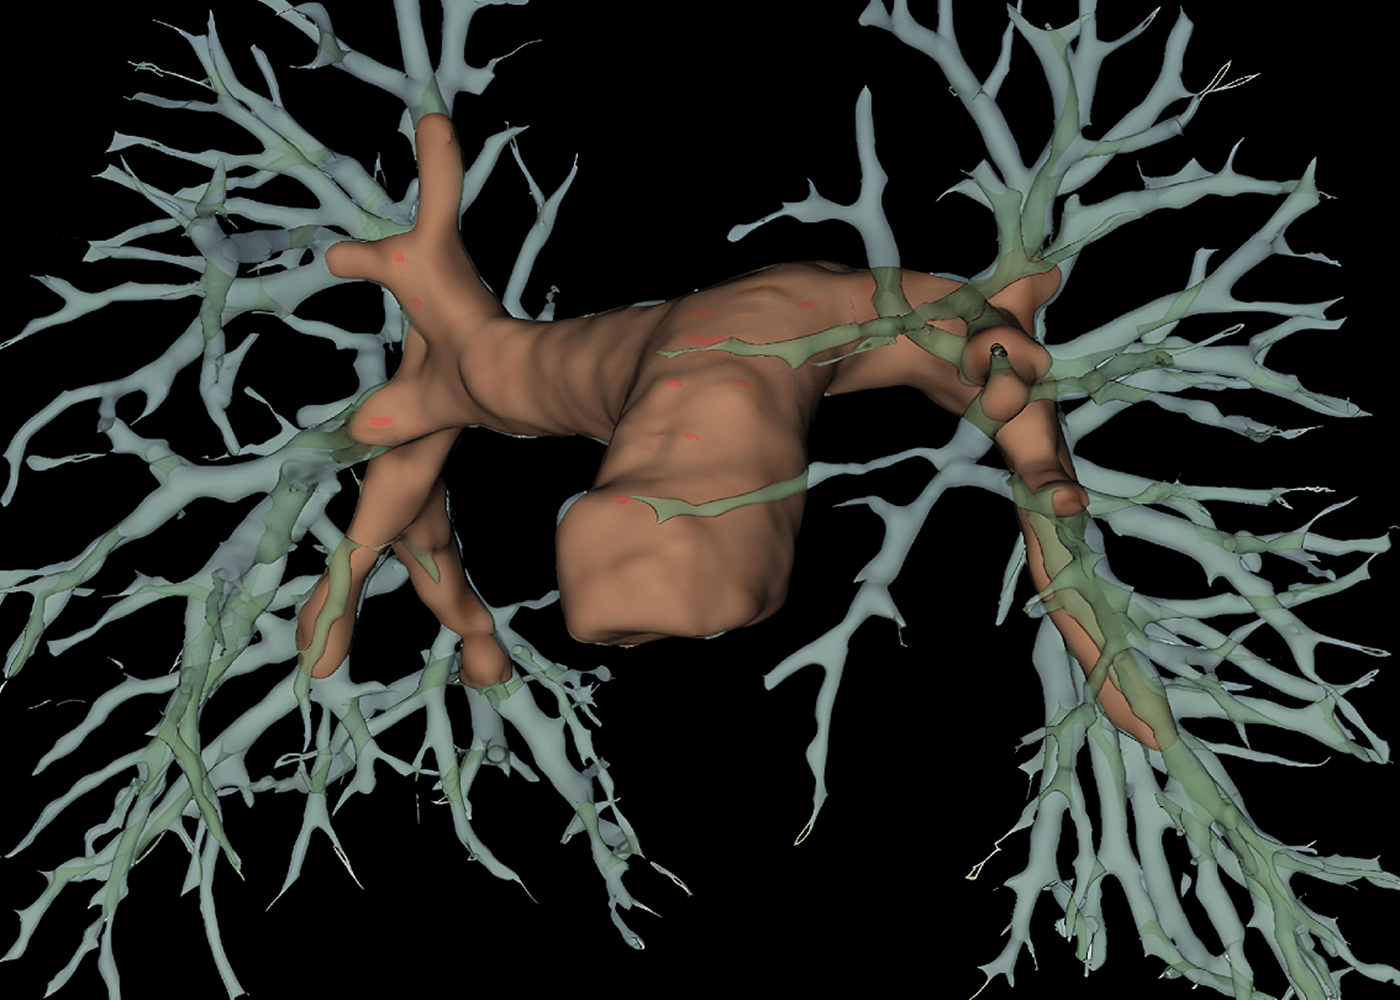

radiology

Pulmonary trunk and arteries segmentation